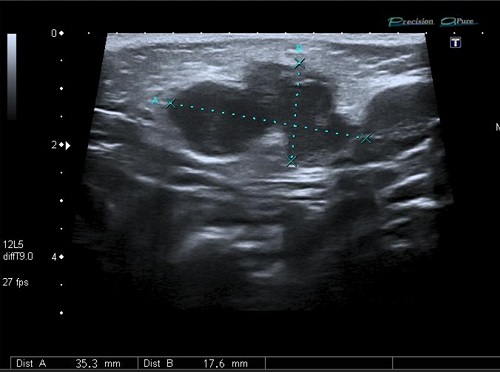

Paciente de 23 meses, mujer, asintomática, que consulta porque los padres detectan una tumoración preauricular derecha 24 horas antes, sin fiebre ni otros síntomas acompañantes. Antecedentes familiares y personales sin interés. Vacunaciones adecuadas para su edad. No alergias conocidas. La exploración es normal, salvo tumoración única preauricular derecha compatible con adenopatía de 1,5 cm de diámetro, de consistencia firme, sin dolor ni eritema. Se aprecia herida a nivel del pliegue anterior del pabellón auricular homolateral. No respuesta a antibiótico (amoxicilina-clavulánico, 7 días). Estudios de hematología, bioquímica, serología de CMV, VEB, virus herpes 6 y toxoplasmosis fueron normales. Prueba de tuberculina a las 48 h negativa. Radiografía de tórax normal. Con sospecha diagnóstica de adenitis por MNT se deriva al hospital, donde, ante un primer hallazgo ecográfico de “adenitis de ganglio intraparotideo derecho con marcada hipogenicidad, a valorar posible abscesificación”, deciden tratamiento con trimetropin-sulmatetoxazol durante 7 días, sin mejoría. Se deriva de nuevo por alta sospecha diagnóstica de MNT, repitiendo ecografía, que se informa: “la lesión palpable corresponde a un ganglio intraparotideo de aproximadamente 1,1 x 1,6 x 1,4 cm; presenta vascularización hiliar prominente y aspecto heterogéneo y marcadamente hipoecoico, con cambios inflamatorios perilesionales. Los hallazgos son compatibles con adenopatía por micobacteria atípica como primera aproximación diagnóstica” (Fig. 4). Se realiza PAAF para cultivo y se aísla M. lentiflavum (antibiograma igual que en el anterior caso, Fig. 2). Dado el riesgo de resistencia a antibacterianos y de dañar la glándula parótida en la extirpación se decide, junto con los padres, la actitud conservadora. A los 2 meses fistuliza con drenaje, dejando en la actualidad, 2 años después, una cicatriz residual (Fig. 5).

Figura 4. Paciente de 23 meses. Ecografía de nódulo intraparotideo por micobacterias no tuberculosas (M. lentiflavum)